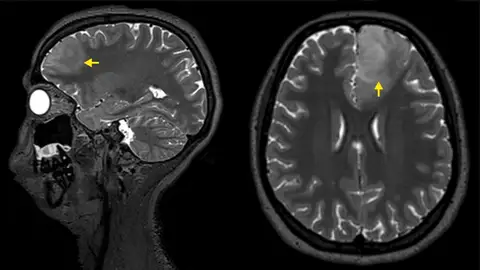

Siete señales de advertencia de tumor cerebral que podrías pasar por alto fácilmente

A todos nos dan dolores de cabeza, se nos pierde el teléfono o se nos olvida un nombre de vez en cuando. La mayoría de las veces, estos momentos son inofensivos: son resultado del estrés, la fatiga o simplemente de una mente ocupada. Pero también son ejemplos de síntomas que, en casos raros, pueden indicar algo mucho más grave: un tumor cerebral.

¿Cómo podemos entonces diferenciar un tumor cerebral de un dolor de cabeza común, del estrés, de una mala noche de sueño o incluso de una resaca? El medio The Conversation revela siete señales de advertencia que podrían pasarse por alto fácilmente. Te contamos los detalles.